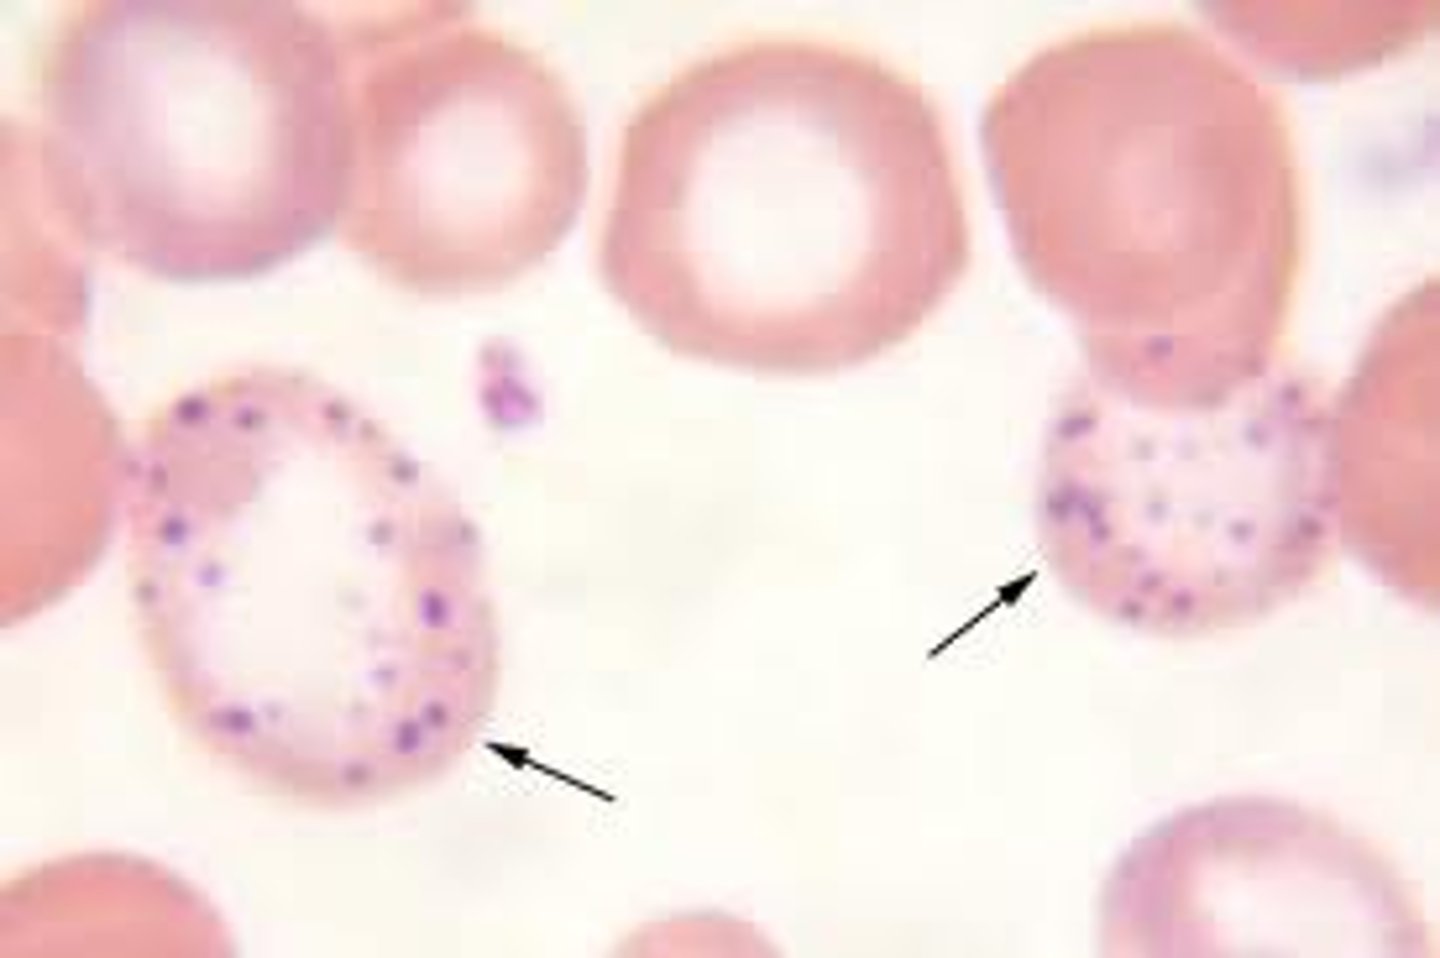

haemoproteus

exotic hemoparasite

nucleus is "embraced" not "displaced"

via blood sucking insects

leucocytozoon

exotic hemoparasite

largest blood parasite

leukocytes and erythrocytes are hosts

plasmodium

exotic hemoparasite

causes avian malaria

via mosquitoes

haemorgregarine

exotic hemoparasite

larger than the hosts nucleus